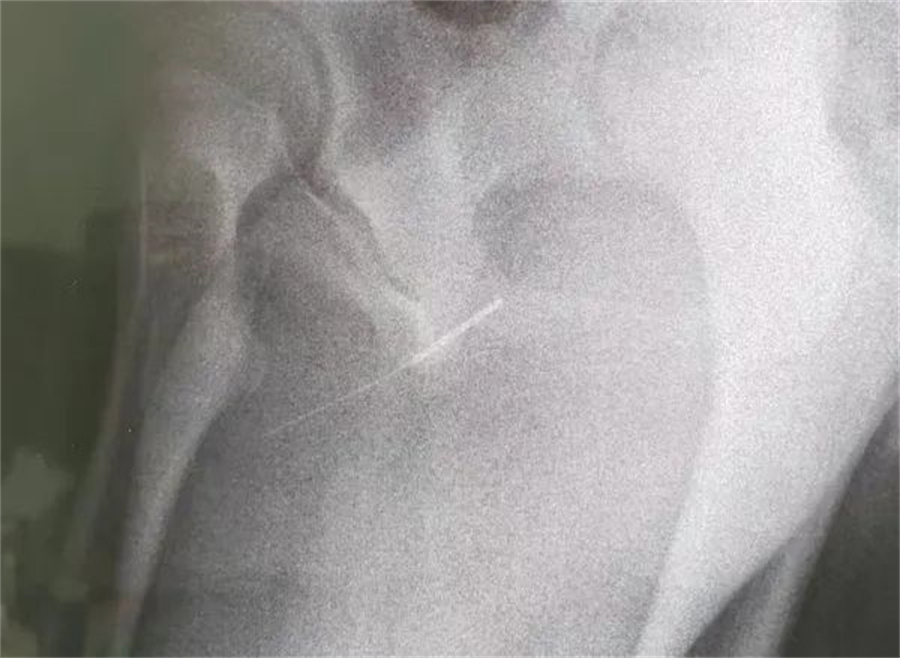

“孩子大概是中午的时候把银针塞进尿道中,因为针灸银针前段柔软纤细而末段又有增粗的螺旋状柄头,所以很难取出来。家长已经带他在当地医院拍片确诊,晚上7点多转到我们医院,当时孩子尿道口有血,疼痛难忍......”啪啪网

急诊外科接诊后立即收入院并第一时间做好手术准备,此时泌尿外科主任谢方达也紧急从家中赶到了医院,经过术前检查,确认银针卡在了接近球部尿道的部位,位置比较深,又没进入到膀胱里,如何尽快地取针成为一个颇具难度的挑战。

孩子家长和泌尿外科专家都希望用最微创的方式完成手术。但因孩子年龄小、尿道细,体重又偏大而难以实现,术中医生在保证对孩子造成伤害最小的前提下,采取隐匿小切口的方式,顺利将6.5cm的银针从尿道中刺破取出,为孩子解除了困扰,术后恢复三四天后即可顺利出院。